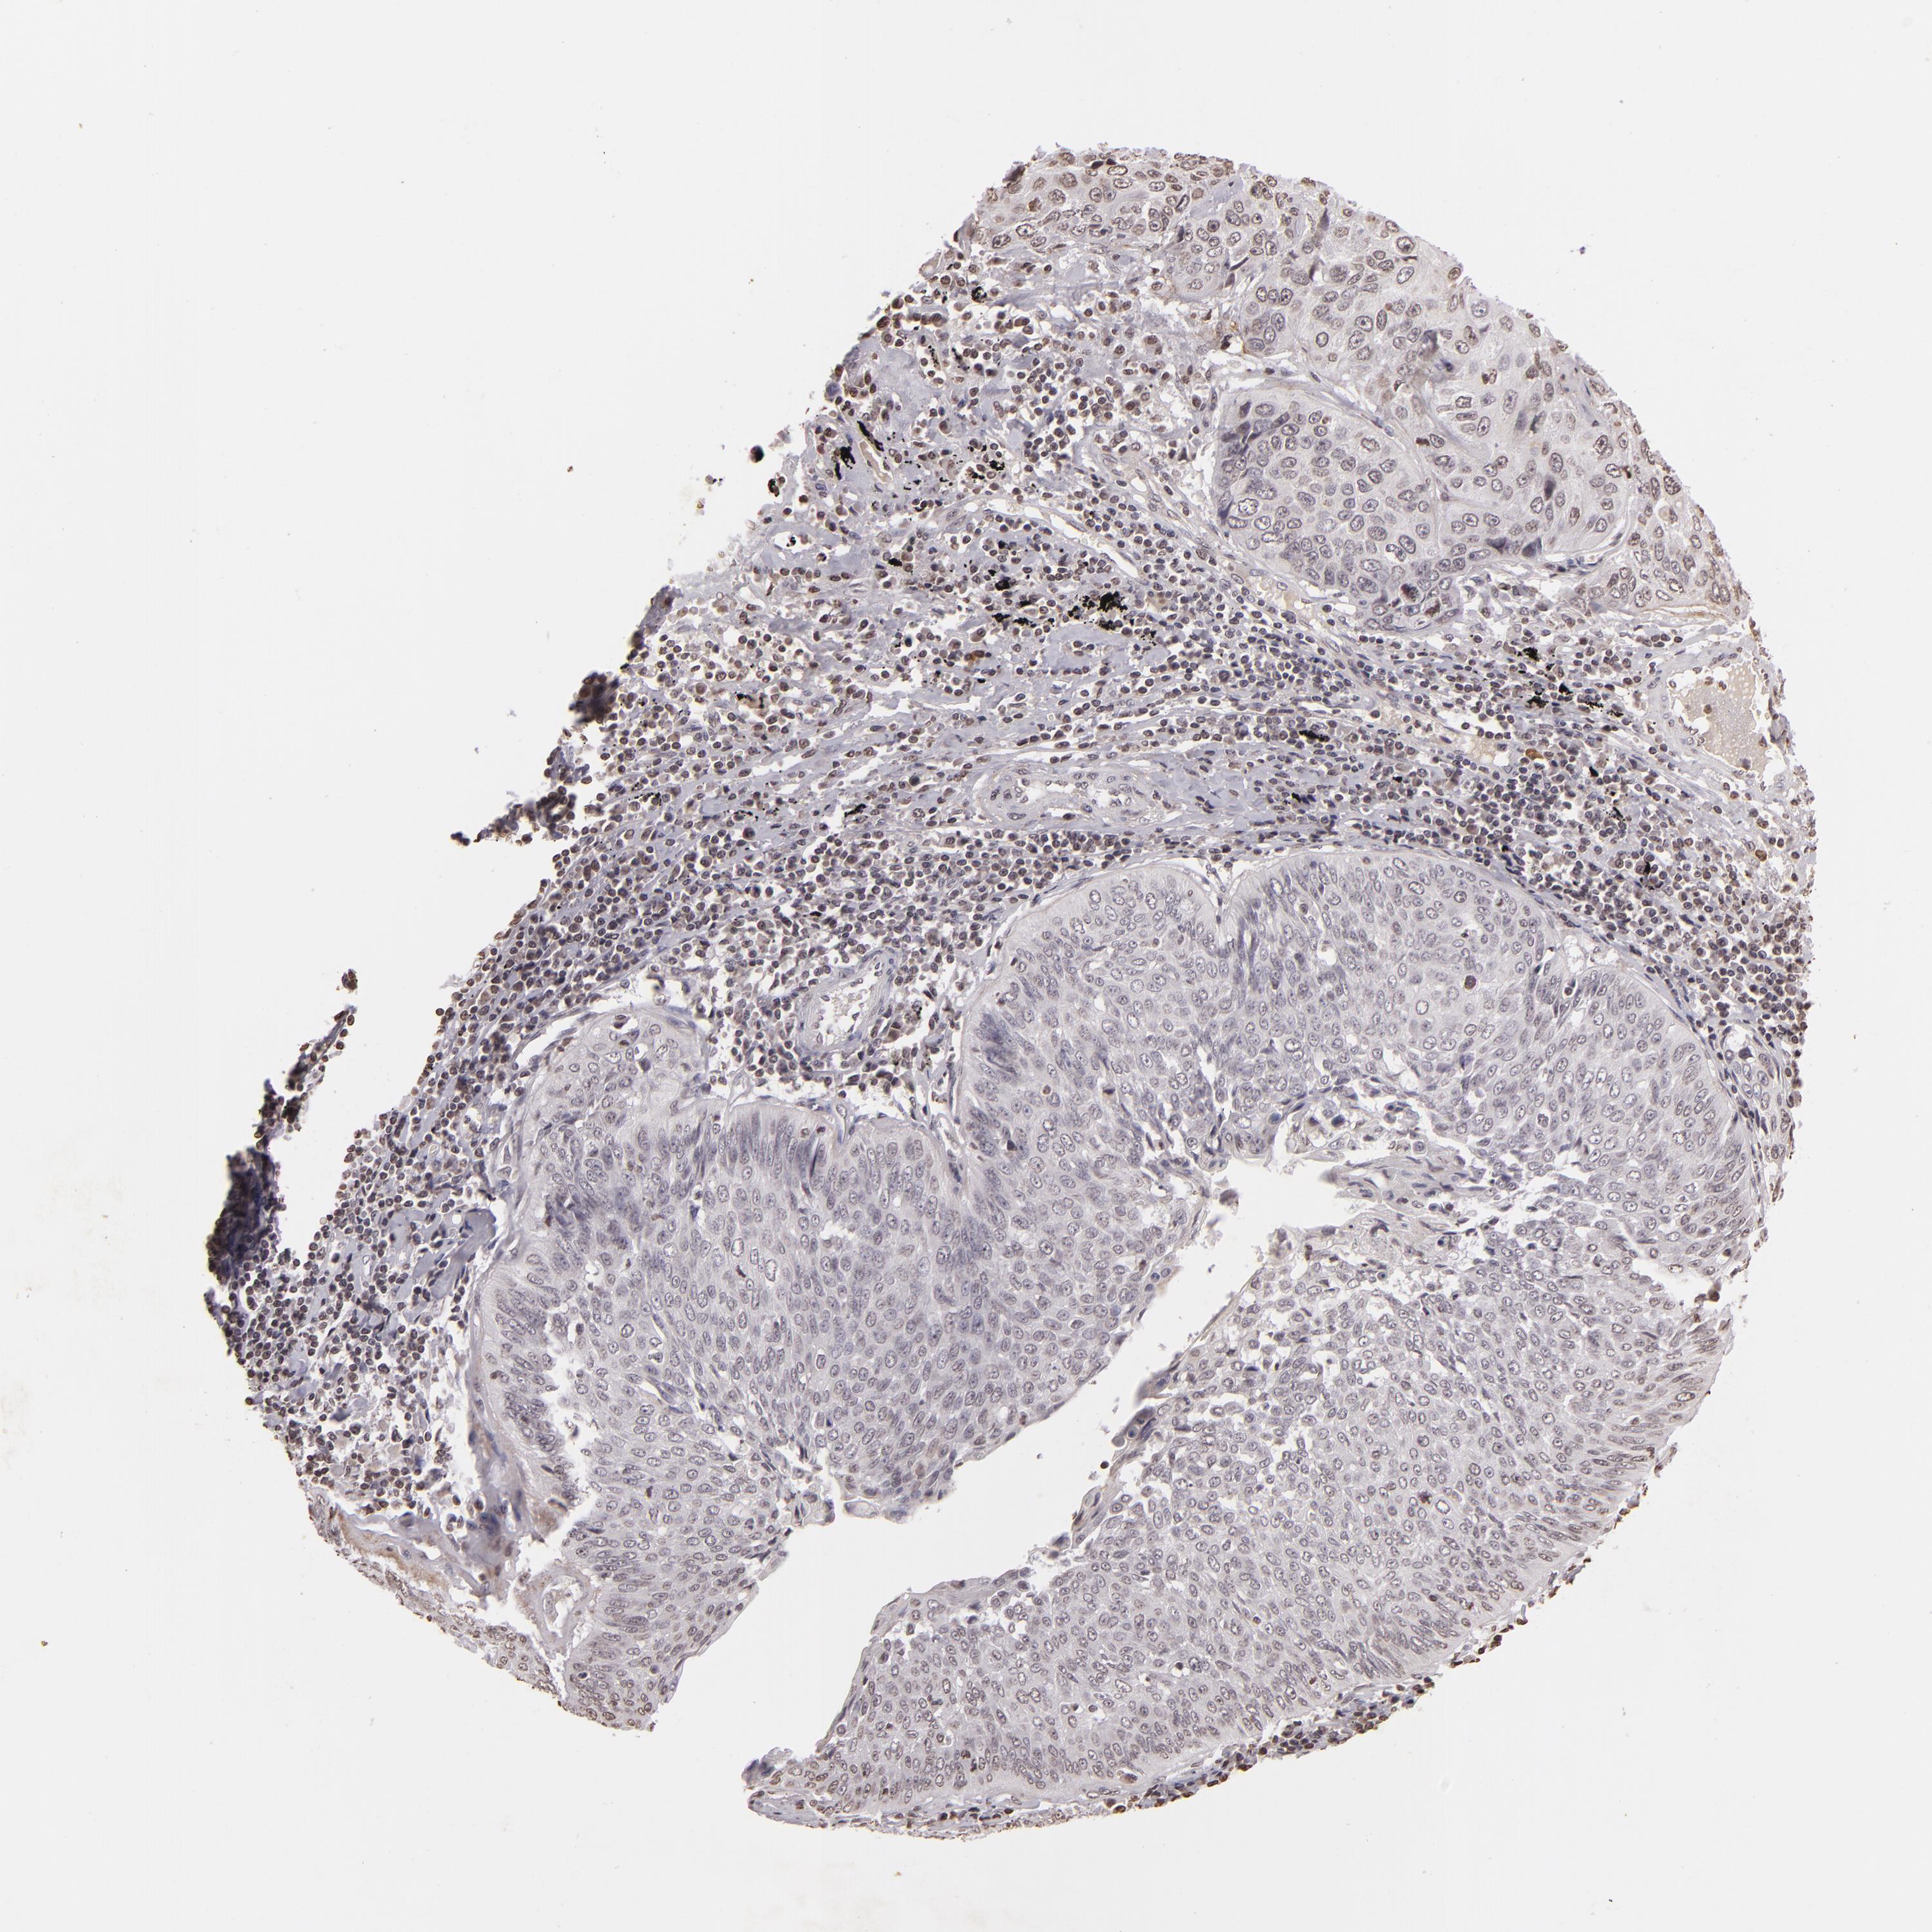

CANCER LUNG CANCER Show tissue menu

LUAD TCGA LUAD VALIDATION LUSC TCGA LUSC VALIDATION PROTEIN LUAD CPTAC PROTEIN LUSC CPTAC PROTEIN EXPRESSION